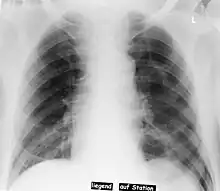

Neumotórax a la izquierda

En una radiografía supina, este signo se ve como un luminoso y profundo ángulo costofrénico ipsilateral,[3] dentro de las porciones no dependientes del espacio pleural en oposición al ápice (del pulmón) cuando el paciente está en posición vertical. El ángulo costofrénico es anormalmente profundo cuando el aire pleural se acumula lateralmente, produciendo el signo del surco profundo.[4]